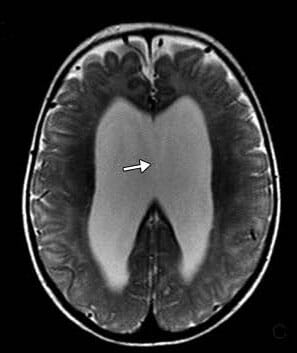

頭部磁気共鳴映像法では、テント上水頭症、視交叉陥凹のバルーニング、薄い脳梁、側脳室および第3脳室の拡張、透明中隔の欠如、および脳の低髄鞘化が明らかになった(図2)。

図2. 磁気共鳴画像法T2強調矢状画像。 脳梁は薄かった。 磁気共鳴画像法T2強調冠状断像。